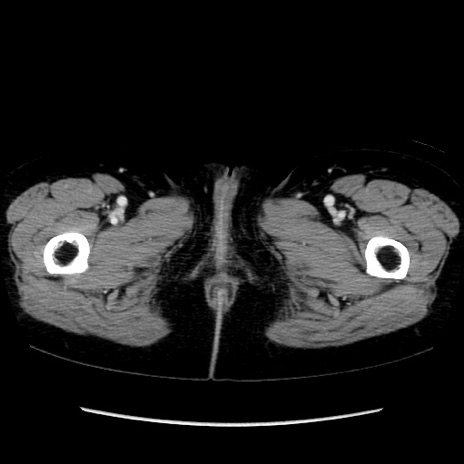

矢状断像